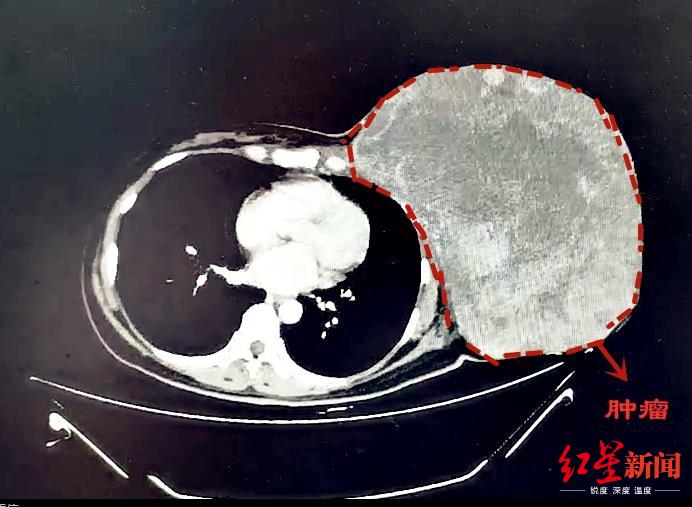

红星新闻从成都市第三人民医院了解到,一颗12斤“巨型”乳腺肿瘤,近日被该院多学科团队顺利摘除。

乳腺肿瘤已成为女性常见的疾病之一。然而,对于47岁的蒋女士来说,她的乳腺肿瘤只能用“心惊胆颤”来形容——直径约30cm、重达12斤!

CT影像

2年多前,蒋女士无意间发现左侧乳腺有一个包块,大约枣子般大小。因为没有疼痛等不适的感觉,她认为“可能问题并不严重”,未进行过系统化的治疗。不过,近半年来她发现包块不仅没有缩小,反而呈现出疯长的趋势。发展到现在,包块已经长到“篮球大小”,严重影响了外观,就连走路等生活日常都存在问题。

针对难点和风险,多学科小组进行了充分的准备及并制定应对措施。9月25日,经过4个半小时的手术精细剥离,将近12斤重的巨型肿瘤才被成功完整摘除。后经病理诊断,确定为交界性叶状肿瘤。经过恢复,近日蒋女士顺利出院。